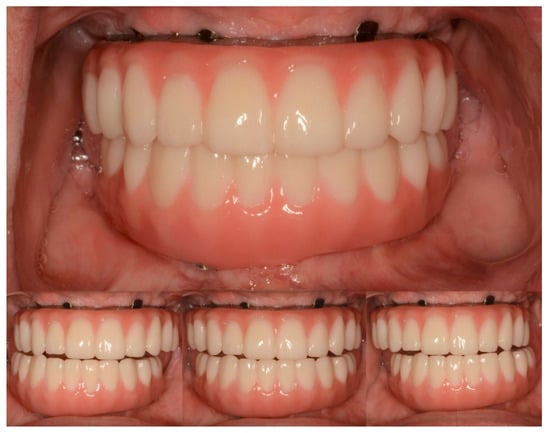

Full-Mouth Rehabilitation of a Patient with Sjogren’s Syndrome with Maxillary Titanium-Zirconia and Mandibular Monolithic Zirconia Implant Prostheses Fabricated with CAD/CAM Technology: A Clinical Report

3. Results